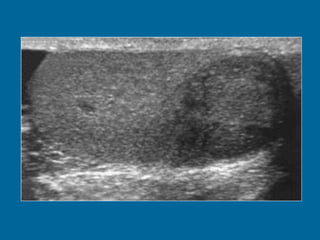

S E M I N O M A Generalidades Supone el 50 % de las neoplasias malignas de testículo. Pico de incidencia entre la cuarta y quinta década. 10% tiene antecedente de criptorquidia. Menor agresividad que otros subtipos histológicos. Quimio y radiosensible. Dentro de la túnica albugínea en el momento del diagnóstico.

Ecografía Masa o nódulo Redondeado u ovoide. Tamaño variable. Ecoestructura homogénea. Hipoecogenicidad. Márgenes parcialmente o mal definidos. Menos frecuentemente con calcificaciones o quistes.

S E MI N O M A Generalidades Supone el 50 % de las neoplasias malignas de testículo. Pico de incidencia entre la cuarta y quinta década. 10% tiene antecedente de criptorquidia. Menor agresividad que otros subtipos histológicos. Quimio y radiosensible. Dentro de la túnica albugínea en el momento del diagnóstico.

Ecografía Masa onódulo Redondeado u ovoide. Tamaño variable. Ecoestructura homogénea. Hipoecogenicidad. Márgenes parcialmente o mal definidos. Menos frecuentemente con calcificaciones o quistes.